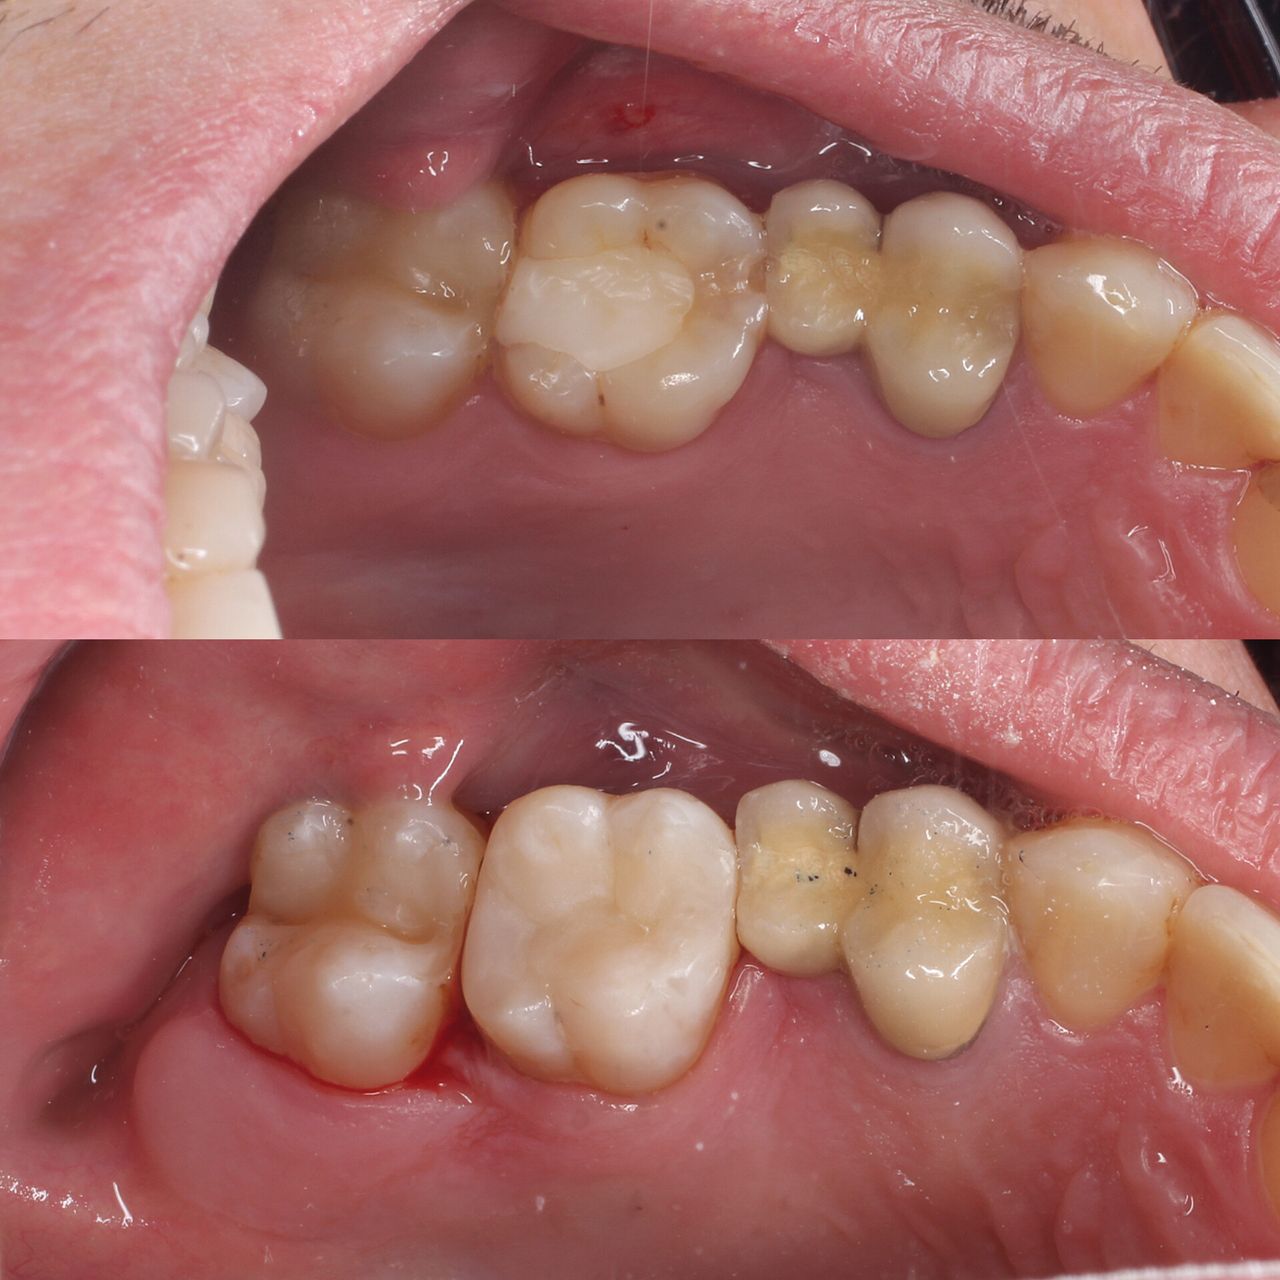

Na co dzień zajmuję się głównie stomatologią zachowawczą oraz leczeniem endodontycznym z wykorzystaniem mikroskopu. Wykonuję leczenie próchnicy i jej powikłań zarówno u dorosłych, jak i u dzieci. Zajmuję się również zabiegami higienizacji, wybielaniem zębów, leczeniem niepróchnicowych zmian szkliwa metodą ICON

Zdjęcia i filmy